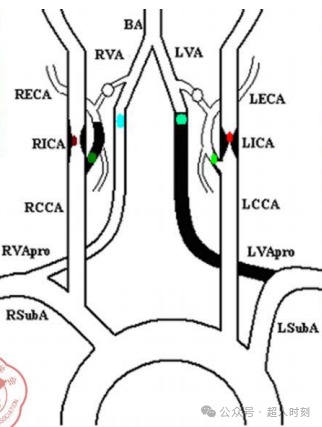

另外,大脑动脉血供(图4)不仅要重视颅内动脉供血情况,也需要关注颅外颈部段血管情况。

图4